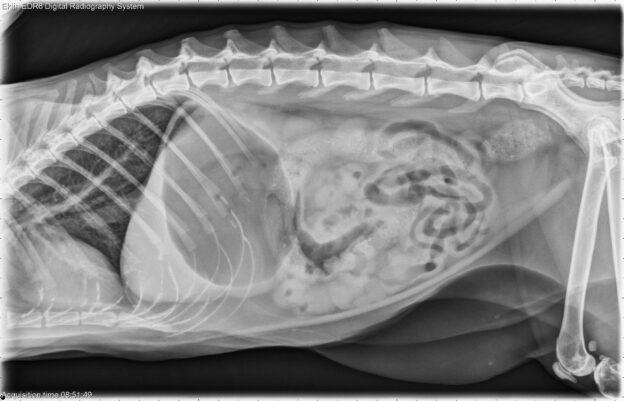

De lesdag wordt aangevuld met online webinars die zelfstandig te volgen zijn. Hierbij komt eerst het acute abdomen aan bod. Dit syndroom kan verschillende oorzaken hebben, waaronder intestinale obstructie, gastro-intestinale bloedingen, torsie van een orgaan (bv. maag, milt, ..), acute pancreatitis etc. Een snelle diagnose en behandeling zijn cruciaal om ernstige complicaties en mogelijk sterfte te voorkomen. Aangezien röntgen foto’s van het abdomen een belangrijke rol spelen binnen de diagnostiek zal je ook een webinar volgen over de interpretatie van abdomen foto’s bij honden en katten met acuut braken. Vervolgens krijg je meerdere oefen quizzen om de geleerde kennis in praktijk om te zetten.

- Radiografie abdomen bij hond/kat met acuut braken